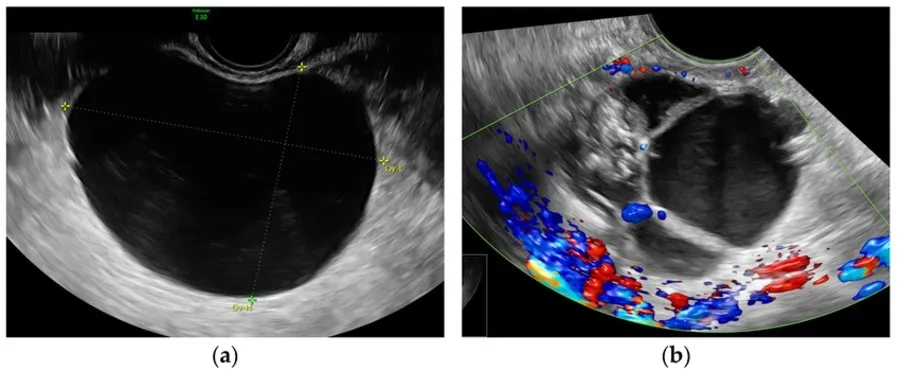

Nang đơn thùy buồng trứng là thuật ngữ chẩn đoán hình ảnh, dùng để mô tả một khối nang ở buồng trứng có cấu trúc chỉ gồm một khoang chứa dịch duy nhất và không có vách ngăn bên trong. Dạng nang này thường được xếp vào nhóm u nang buồng trứng dạng đơn giản. Trên siêu âm, nang đơn thùy thường có thành mỏng, bờ rõ và bên trong chứa dịch, vì vậy hình ảnh hiển thị khá đồng nhất.

Hình ảnh siêu âm so sánh nang buồng trứng đơn giản, một ngăn, không phản âm (a) và nang buồng trứng phức tạp (b)

Siêu âm phụ khoa là phương pháp quan trọng giúp phát hiện và đánh giá đặc điểm của các khối nang buồng trứng. Thông qua hình ảnh siêu âm, bác sĩ có thể nhận biết cấu trúc của nang, từ đó phân biệt nang đơn thùy với các dạng nang phức tạp hơn và đánh giá bước đầu nguy cơ lành tính hay bất thường.

Nang đơn thùy thường có một số đặc điểm hình ảnh điển hình sau:

- Chỉ có một khoang dịch duy nhất, khối nang không bị chia thành nhiều ngăn và không xuất hiện các vách ngăn bên trong.

- Thành nang mỏng và bờ rõ, đường viền của nang đều, không gồ ghề hay dày bất thường.

- Bên trong chứa dịch nên hình ảnh echo trống: Cấu trúc bên trong nang thường đồng nhất, không có mô đặc.

- Không có nốt sùi hoặc thành phần đặc: Đây là đặc điểm quan trọng giúp gợi ý tính chất lành tính của nang.

- Kích thước nang có thể thay đổi: Nhiều nang nhỏ có thể tự thoái triển sau vài chu kỳ kinh nguyệt.